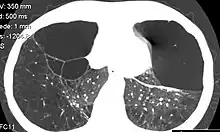

Pulmones enfisematosos con bulas (burbujas negras con paredes finas) en una tomografia por DA1AT.

Las bullas en el paciente con enfisema pulmonar se caracteriza por la existencia de amplias áreas de pulmón hiperclaro surcadas por tractos lineales curvilíneos que no corresponden a ninguna estructura anatómica reconocible y que correspondan a las propias paredes de las bullas[2]